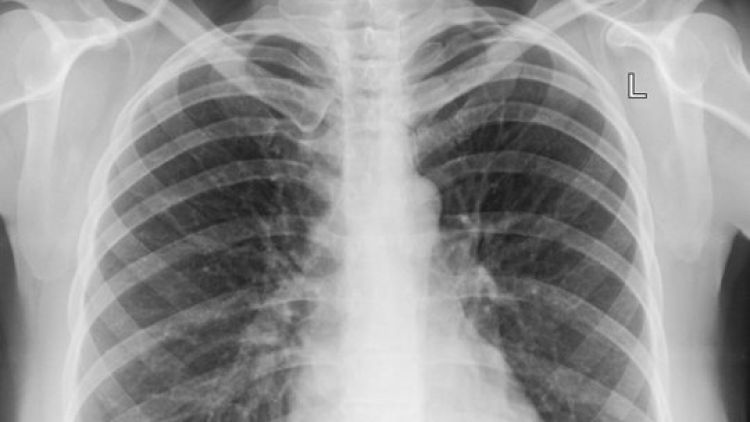

O empresário natural de Minas Gerais, mas que mora em Parnaíba, Oderman Bittencourt, proprietário da Delta Laticínios, está encontra-se em Teresina em tratamento de uma grave pneumonia pelo vírus Influenza H1N1. Por meio de nota, a assessoria do empresário informou ainda que o mesmo está reagindo bem ao tratamento e que logo retornará as suas atividades, esclarecendo que os exames médicos testaram negativo para infecção por Coronavírus (Covid-19).